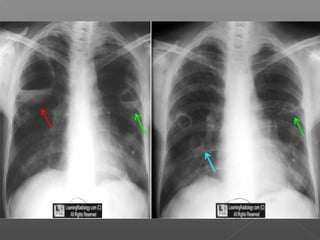

•Pulmonary nodules

– Chest CT every 6-12 months

Necrotizing Granuloma Hypereosinophilia •Sinusitis •Subglottic stenosis •Pulmonarynodules •Orbital pseudotumor •Asthma •Pulmonary infiltrates •Myocarditis •Pulmonary capillaritis •Glomerulonephritis •Sensory neuropathy •Mononeuritis multiplex

 Potentially fatalvasculitis involving small vessels  Rare: 3-14/million, more common in whites, any age but rare in children  Pathology shows necrotizing granulomas usually in upper airways, lungs and kidneys